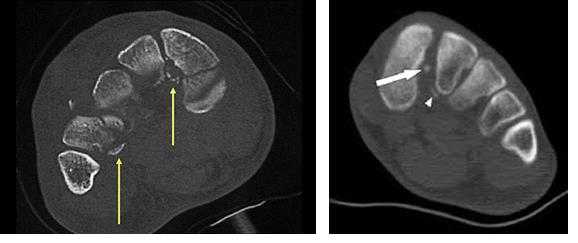

о Во многих случаях исследование стопы лучше выполнять в положении пациента лежа на животе(Слева) При МРТ по длинной оси плюсневых костей на Т1ВИ определяется неизмененный межкостный пучок связки Лисфранка, натянутый между латеральным краем медиальной клиновидной кости и медиальным краем 2-й плюсневой кости. Следует отметить, что 2-й предплюсне-плюсневый сустав сдвинут относительно 1-го и 3-го предплюсне-плюсневых суставов, в результате чего образуется соединение по типу «шип-паз», способствующее стабилизации сустава.

(Справа) У другого пациента при МРТ по длинной оси плюсневых костей на том же уровне на ППВИ в режиме FS визуализируется разрыв межкостного пучка связки Лисфранка. (Слева) При МРТ по короткой оси плюсневых костей на Т2ВИ в режиме FS различимы три пучка связки Лисфранка: тыльный, межкостный и подошвенный. Следует отметить, что межкостный пучок напоминает канат, поскольку в его структуре выявляется множество волокон, а тыльный и подошвенный пучки выглядят в виде тонкой ленты.

(Справа) При МРТ по короткой оси плюсневых костей на Т2ВИ в режиме FS визуализируется разрыв тыльного, межкостного и подошвенного пучков связки Лисфранка. Коронарная плоскость позволяет оценить выраженность повреждения связки. (Слева) При рентгенографии среднего отдела стопы в передне-задней проекции определяется неизмененный 2-й плюсневый сустав. Медиальный край 2-й плюсневой кош находится на одной линии с медиальным краем промежуточной клиновидной кости. Даже небольшое смещение данных костей относительно друг друга свидетельствует о повреждении связки Лисфранка.

• Поскольку при КТ исследование с нагрузкой не проводят, смещение плюсневой кости может визуализироваться хуже, чем при рентгенографии5. МРТ при повреждении связки Лисфранка:

• Признаки повреждения связки визуализируются в аксиальной и коронарной плоскостях:

о Позволяет легко различить три пучка связки Лисфранка

о Подошвенный и тыльный пучки тонкие и напоминают ленту

о Межкостный пучок имеет большую толщину и характеризуется наличием различимых волокон

• Часто в медиальной клиновидной или 2-й плюсневой кости обнаруживают отек костного мозгав) Дифференциальная диагностика повреждения связки Лисфранка:

(Справа) При МРТ по длинной оси плюсневых костей на ППВИ в режиме FS визуализируется разрыв межкостного пучка связки Лисфранка. Несмотря на то что подвывих предплюсне-плюсневого сустава является специфичным для повреждения связки Лисфранка, следует помнить о том, что достаточно часто при рентгенографии получают ложноотрицательный результат. (Слева) У этого же пациента при МРТ по длинной оси плюсневых костей на ППВИ в режиме FS определяется разрыв тыльного пучка связки Лисфранка.

(Справа) У этого же пациента при МРТ по короткой оси плюсневых костей на Т2ВИ в режиме FS визуализируется разрыв тыльного и межкостного пучков связки Лисфранка. Подошвенный пучок растянут, однако целостность его сохранена. При осмотре с анестезией была обнаружена нестабильность 2-го предплюсне-плюсневого сустава.г) Патология: